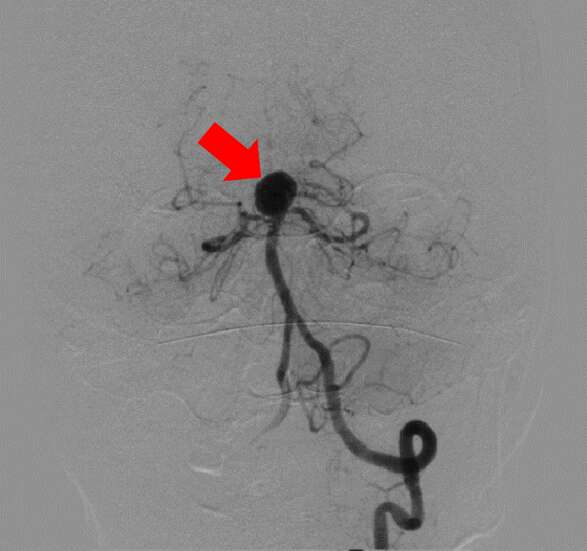

【治療例2:脳動脈塞栓術】

カテーテルを用いて、脳動脈を詰める治療で

す。瘤内部にコイル(金属製の柔らかい針)を幾重にも巻いて血流がなくなるまで詰めていきます。

治療前

赤矢印が脳動脈瘤

治療後

コイルを詰めて血流を遮断